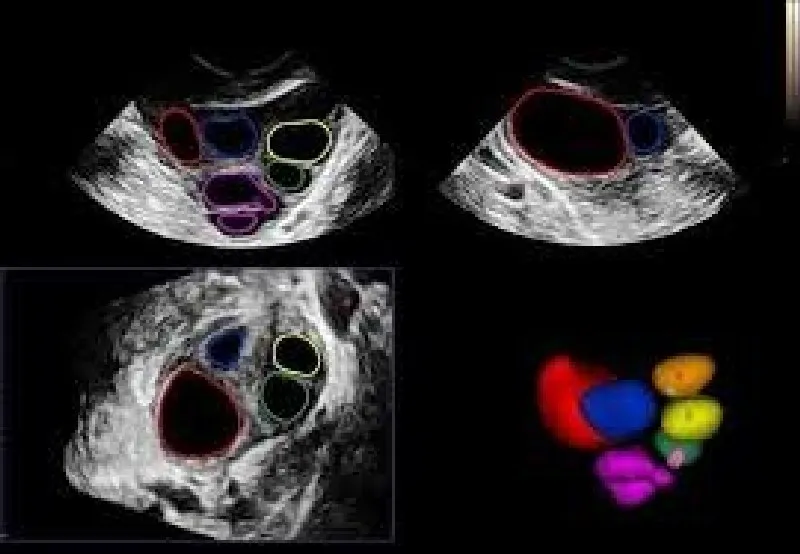

Com a possibilidade de ser alugada com uma empresa de outsourcing de impressão de alta confiabilidade, a impressora de ultrassom proporciona que as imagens deste exame, formadas por meio das ondas sonoras emitidas e captadas durante o processo, sejam impressas em alta qualidade no papel fotográfico, eliminando a necessidade de impressão em filme dry. O processo realizado com a impressora de ultrassom é veloz e permite que o profissional de medicina altere as imagens do exame antes da impressão, melhorando elementos como cor e contraste. Todos estes fatores contribuem para um diagnóstico mais rápido e preciso, o que beneficia o paciente e otimiza o tratamento.